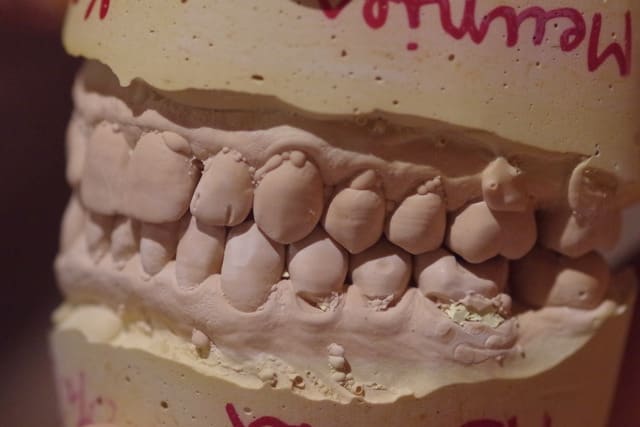

1) Si la cinématique mandibulaire est symétrique

2) Si les deux arcades sont toujours coordonnées (avec les modèles sur le plan de travail!) Si c'est le cas penchons pour l'hypothèse de Sethef (luxation). Si le couvercle ne va plus avec la boîte penchons pour l'hypothèse fonctionnelle (la tienne).

J’ai mis des photos des modèles qui n’arrivent pas bien sur à être en occlusion.

Le patient occluse uniquement côté droit au niveau prémolaire et molaire.

Je me suis amusé aussi à mettre en occlusion les modèles côté G ( comme on voit sur une photo) et bien évidemment le côté droit était en inocclusion.